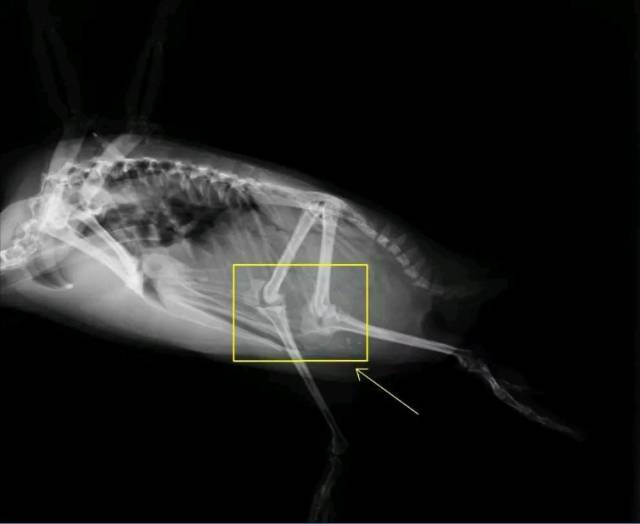

鸡的膝盖为什么往后弯

不光是鸡,所有的鸟类,看起来膝盖都是往后弯的。这是为什么呢?

因为它们的腿和我们结构不太像。好,现在请你站起来,做一个踮脚的动作。感受一下。所有的鸟类,它们的脚相当于我们的腿踮起来:踮起之后,我们的脚趾和前脚掌,相当于鸟的脚掌;我们的前脚掌到脚踝的部分,相当于口语中鸟的小腿或琵琶腿;我们的小腿,相当于鸟的大腿;而我们的大腿,就是更上面大的那一截。

所谓“鸡的膝盖向后弯”,真相是,那不是膝盖,那是鸡的脚后跟。

鸵鸟和人的腿骨对比。

鸡站立时腿部的姿势,和我们踮着脚蹲下来差不多。